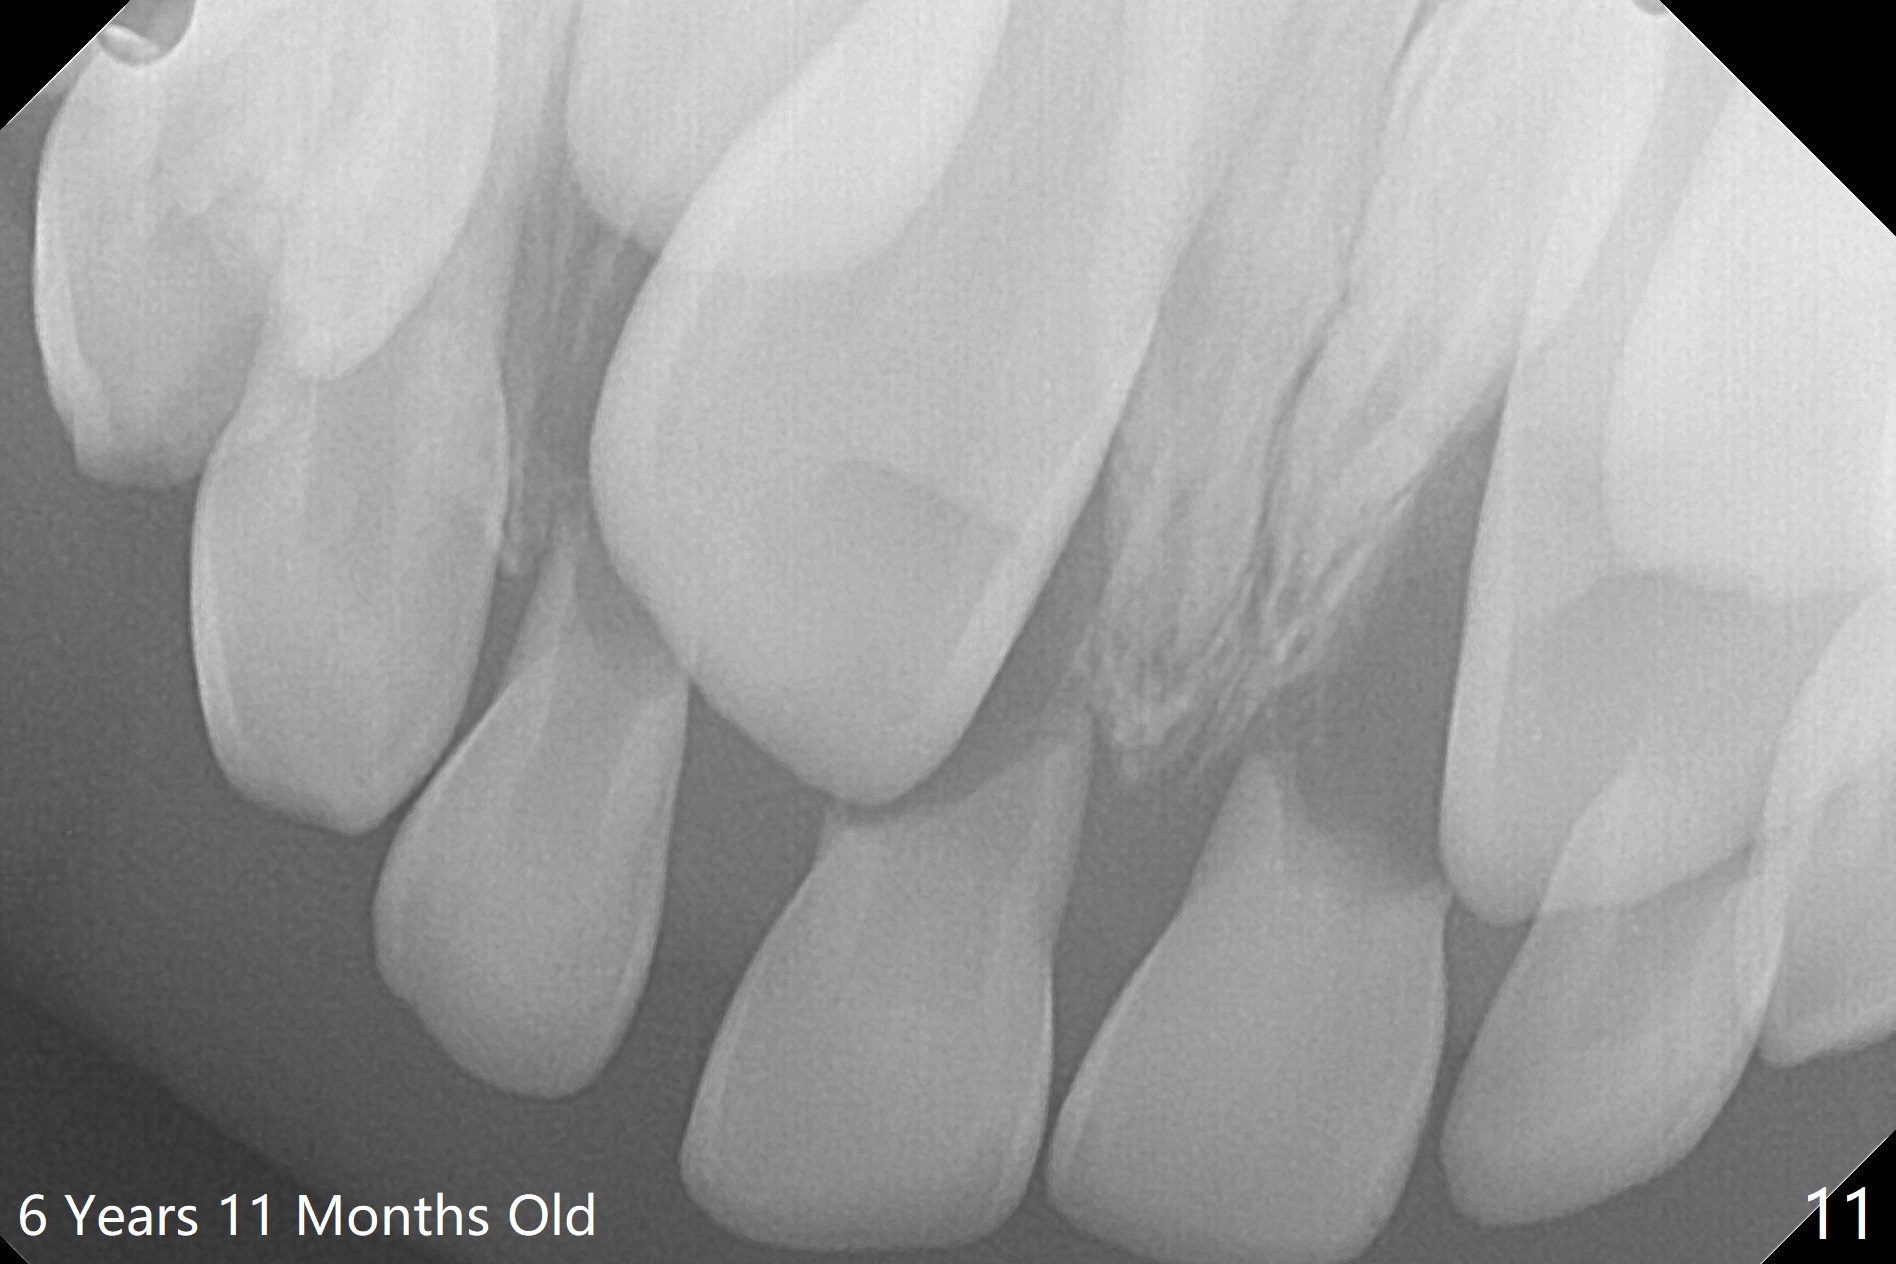

While the lower centrals are erupted and the lower laterals are erupting, the upper deciduous centrals are mobile 6 years 11 months old.  It appears that the upper centrals are divergent and causes root resorption of the decidous incisors (Fig.11).